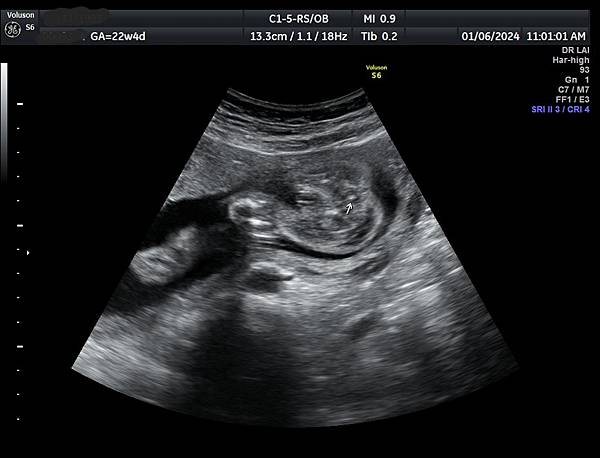

針對部分胼胝體發育不全的診斷,需要非常小心,如果胼胝體只有1/3的個案比較不會是假的,如果是2/3的個案就要很小心判斷是否過度診斷,我喜歡把胼胝體當做第五腦室(CSP )及第六腦室(cavum vergae )的天花板,CSP 與cavum vergae的比例大約2:1,通常CSP 和cavum vergae 都是黑黑的(附圖1),這樣的情況不會量錯,如果cavum vergae呈現白白時(echogenicity),它的天花板就很有可能被誤判不屬於胼胝體,這個問題我已經遇過很多類似的案例,例如附圖2~4是同一個case,圖4沒有疑慮,圖2及圖3很有可能只量到前面2/3比較明顯的部分,而沒有量到圖上的數據。